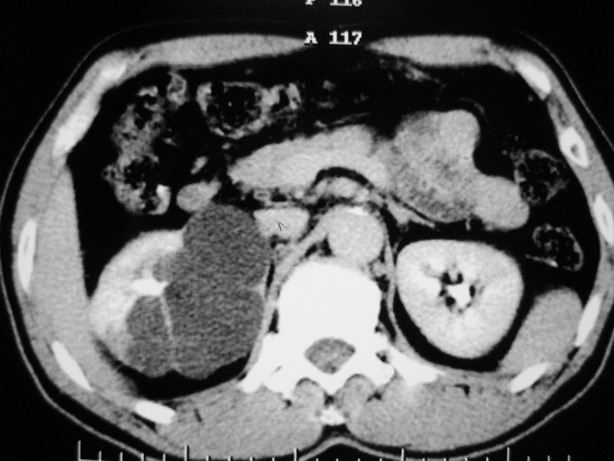

标题: CT10772:男性,48,右肾盂旁多囊性占位! [打印本页]

标题: CT10772:男性,48,右肾盂旁多囊性占位!

男性,48,体检发现,平时无症状。

平扫:

肾盂旁多囊性占位,有实性成分,增强有轻度强化,收集期病变内无造影剂显影。诊断肾盂旁囊肿,有实性成分无法解释,查书后诊断为:多房性囊性肾瘤!!不知大家同意否?????????对本病知道不多,望大家不吝赐教!!